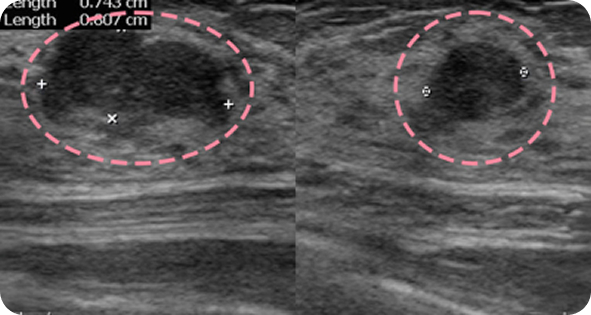

맘모톰시술 후 병리조직검사 결과 상피내암(조기 유방암)

초기로

진단되어 항암치료 없이 간단한 수술로 치료가

가능했습니다. 눈에

잘 띄지 않는 작은 병변까지 확인할 수 있었던 건,

맘모톰의 정밀한

조직검사 기능과 전문의의 정확한 판독이 있었기 때문입니다.

외국에서 내원한 17세 환자분은 빠르게 자라는 큰 유방 종양으로 대학병원 수술이 권고되었으나, 고난도 시술 경험을 바탕으로 3차례 맘모톰을 통해 성공적으로 제거했습니다. 흉터를 걱정했던 환자와 보호자 모두 결과에 만족하며, 현재까지 정기 추적검사에서 깨끗한 상태를 유지하고 있습니다.